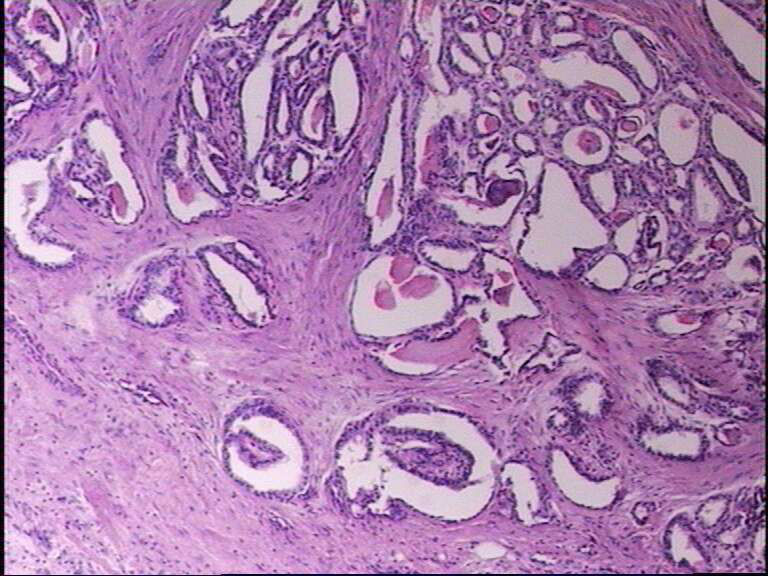

女43岁,甲状腺肿物